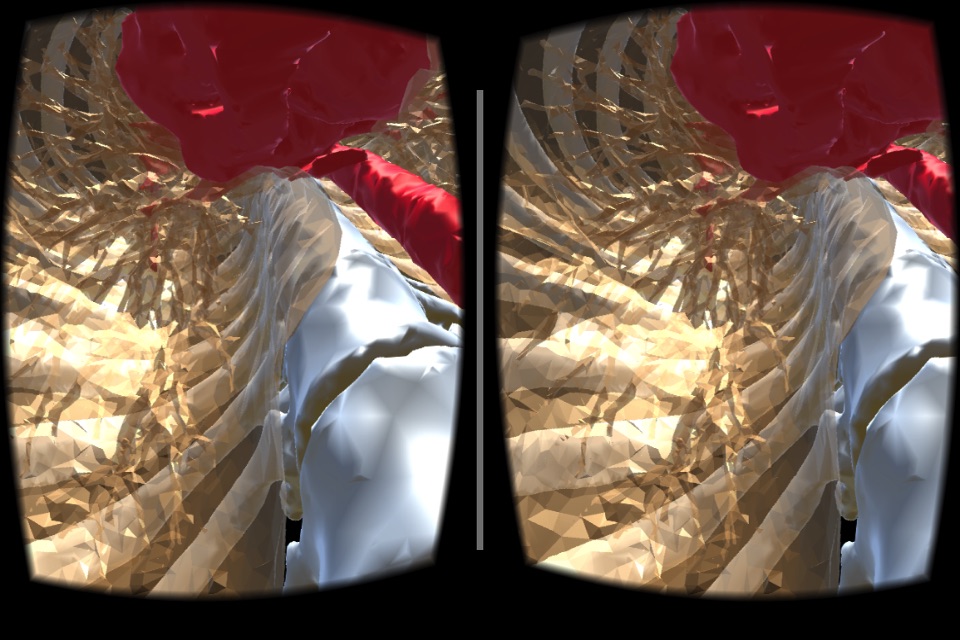

VR Body Guideは、まるで目の前にあるように、

人体の内部の様子をリアルに眺めて、

人体の不思議を楽しむことができる、医学教育用アプリです。

実際のCT画像から起こされた、本物の内臓のモデルを、間近に見ることができます

(これは似せて作られたモデルではありません!)。

・鑑賞するモデルは「頭部」と「胴体」の2種類です。

一方、胴体は、心臓、骨、皮膚をそれぞれON/OFFすることができます。